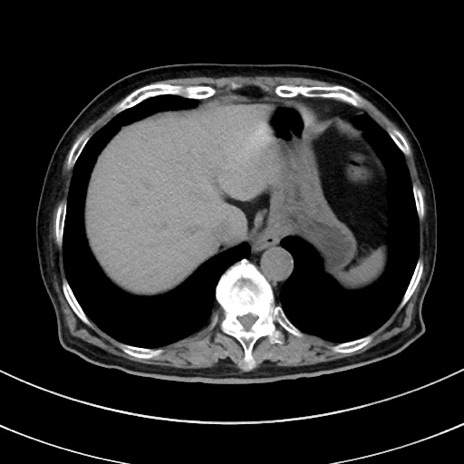

症例33(横断像)

【症例】70歳代 女性

【主訴】心窩部痛

【現病歴】延髄病変の精査・加療にて神経内科入院中。本日より心窩部痛あり。

【身体所見】右下腹部を中心に圧痛と反跳痛あり。

【データ】WBC 10900、CRP 0.02